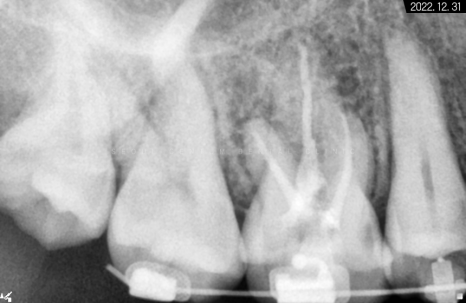

보통 어금니는 뿌리가 3~4개인 경우가 많아

신경 치료 시간이 조금 더 오래 걸리고

뿌리 형태도 휘어진 곳이 많다보니

앞니보다 난도 높은 술기에 해당합니다.

*기다란 막대기는 뿌리 끝 길이를

측정하기 위해 사용한 도구입니다.

교합면 우식을 제거하면서 근관 입구에 접근 후

근관장 길이 측정과 오염원 소파 및

소독 재료를 이용해서

근관을 멸균 상태로 만들고

그 후 안정 물질로 뿌리 끝까지

꼼꼼하게 메꿔드렸습니다.

그렇게 해서 3개의 뿌리가

흰색으로 잘 완성된 것을 볼 수 있습니다.

충전재로 잘 채워져 있고

레진으로 밀봉까지 마무리해두어서

하얗게 보이고 있는 것입니다.

다행히 뿌리가 막혀있지 않고